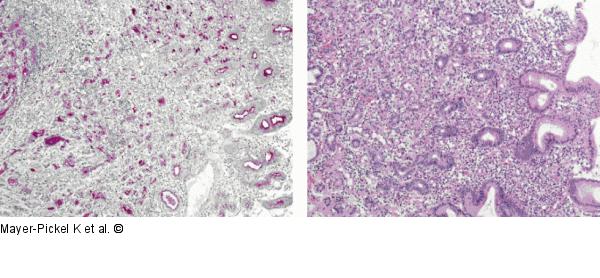

Abbildung 3a-b: Magenkarzinom Niedrig differenziertes Adenokarzinom des Magens |

Abbildung 3a-b: Magenkarzinom

Niedrig differenziertes Adenokarzinom des Magens |